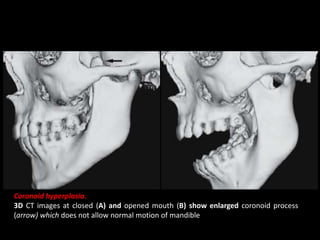

Coronoid hyperplasia.

3D CT images at closed (A) and opened mouth (B) show enlarged coronoid process

(arrow) which does not allow normal motion of mandible